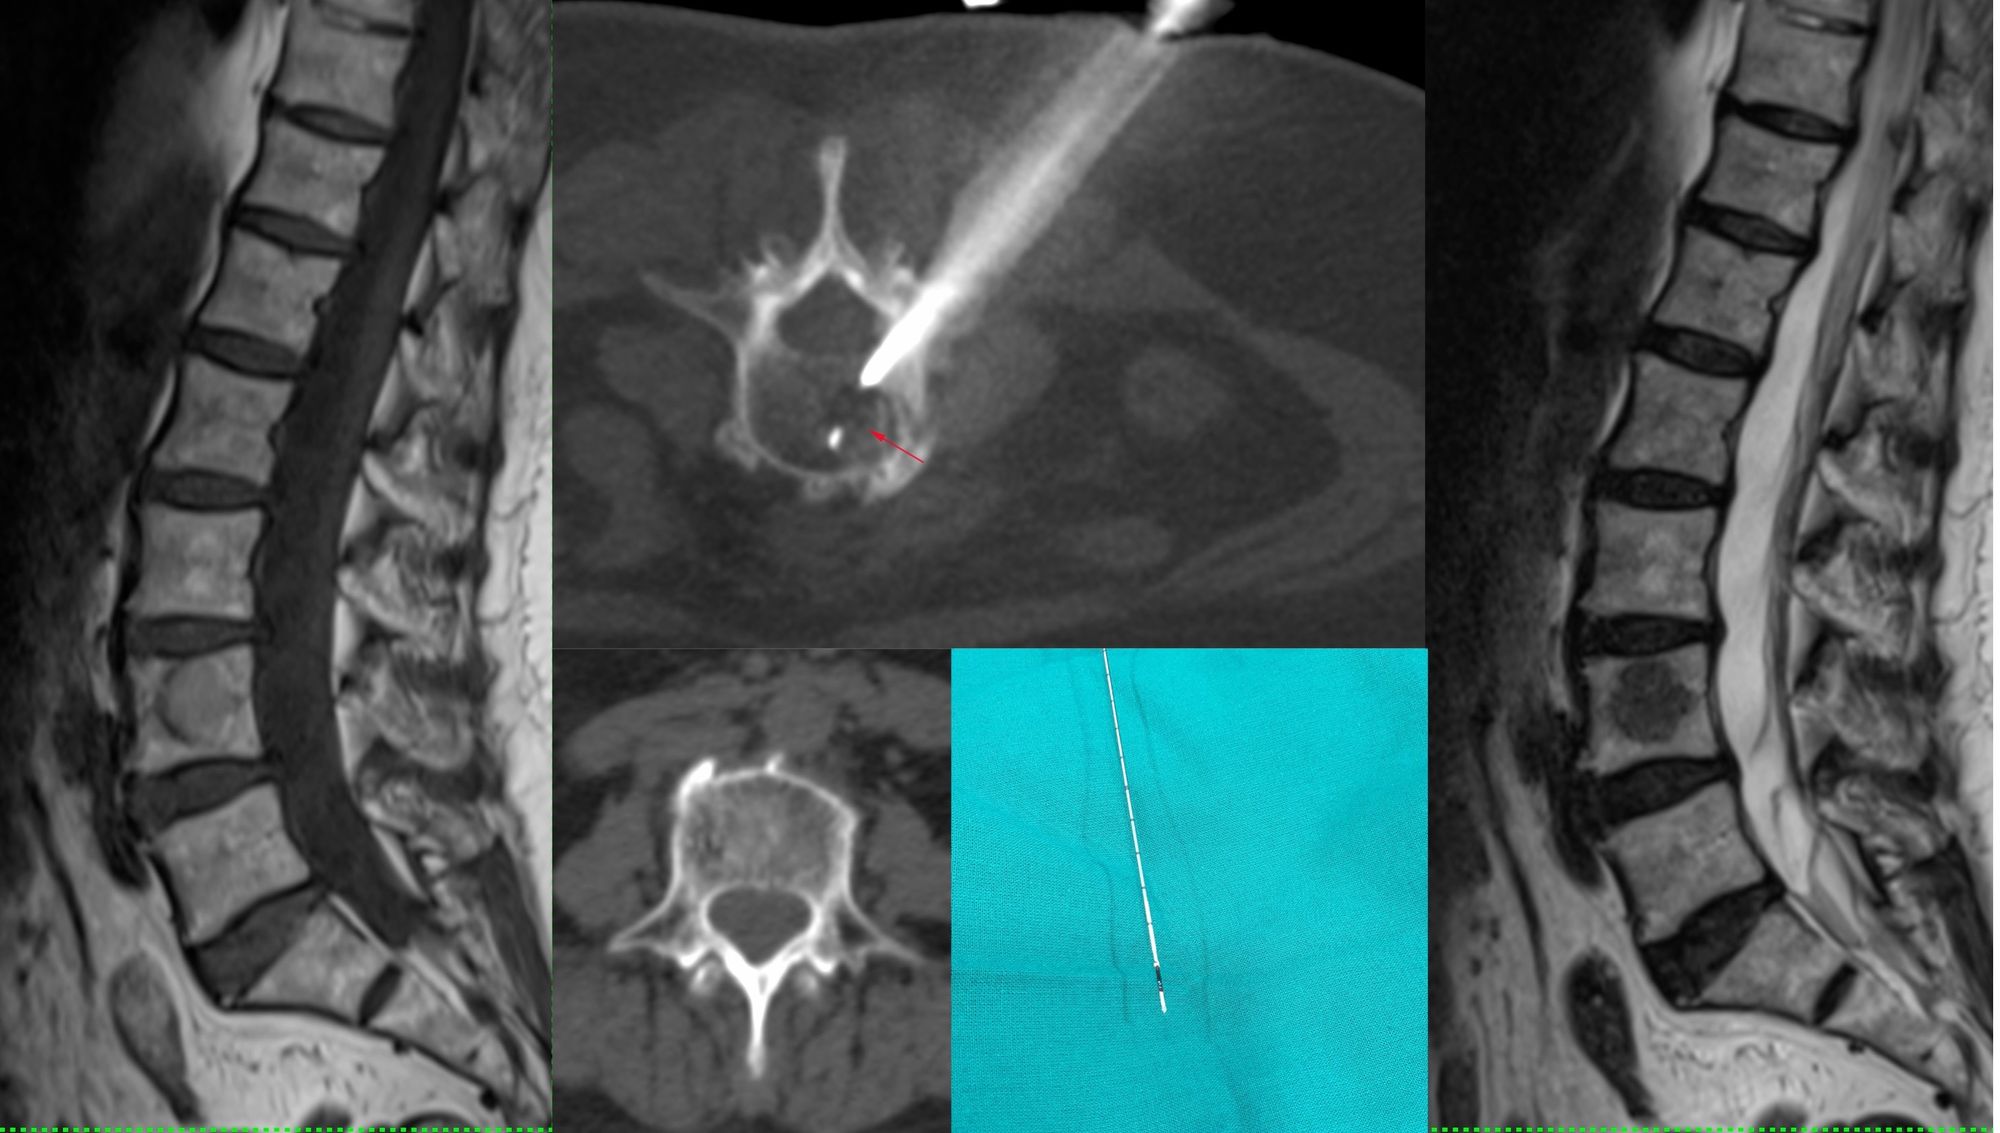

Case 49: When The Answer is in the Biopsy Material Itself – Vertebral Melanoma Metastasis

Bhavin Jankharia - 16 July 2021